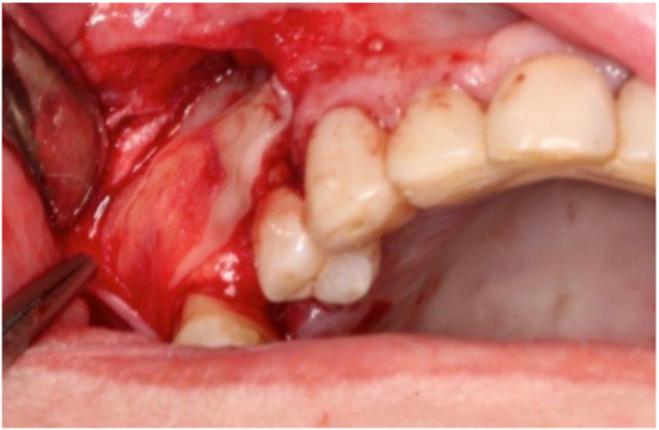

After tooth loss in the posterior area of the maxilla, sinus floor elevation is often required to compensate the vertical bone loss due to sinus pneumatization. This narrative review reports on the potential benefits of autologous platelet concentrates (APCs) during this procedure. As for transcrestal approach, APCs have been used as "sole" substitute/graft. However, because of the low number of clinical trials available with PRGF, and even none for PRP, no definitive conclusions can be made regarding their efficacy. The number of studies on the use of L-PRF were outnumbered indicating good feasibility for vertical bone gain, with a high implant survival rate and a low degree of complications. PRP and PRGF have not been studied as a "single/sole" substitute for a one-stage lateral window approach, probably because of the weak physical characteristics of the membranes. L-PRF alone appears to be a predictable grafting material for lateral maxillary sinus grafting and a reduced RBH should not be considered as a risk factor. Compared to a "standard" bone substitute L-PRF shows slightly less vertical bone gain (consider enough membrane application and use of bony window as new sinus floor roof over the implant apices), enhanced early resorption (first 6 months after application), but a similar stable bone gain afterward. For a two-stage lateral window approach, APCs "alone" cannot be recommended, due to their weak withstand to the sinus pneumatization forces. APCs combined with bone substitutes seem to accelerate bone formation, without any additional benefits on the long-term new bone gain. The use of L-PRF membranes for the treatment of perforations appears to be an effective treatment option, but further clinical studies are needed to confirm this. Even though the abovementioned statements are based on large numbers of studies, additional RCTs comparing APCs with different types of grafting procedures for sinus elevation are needed.